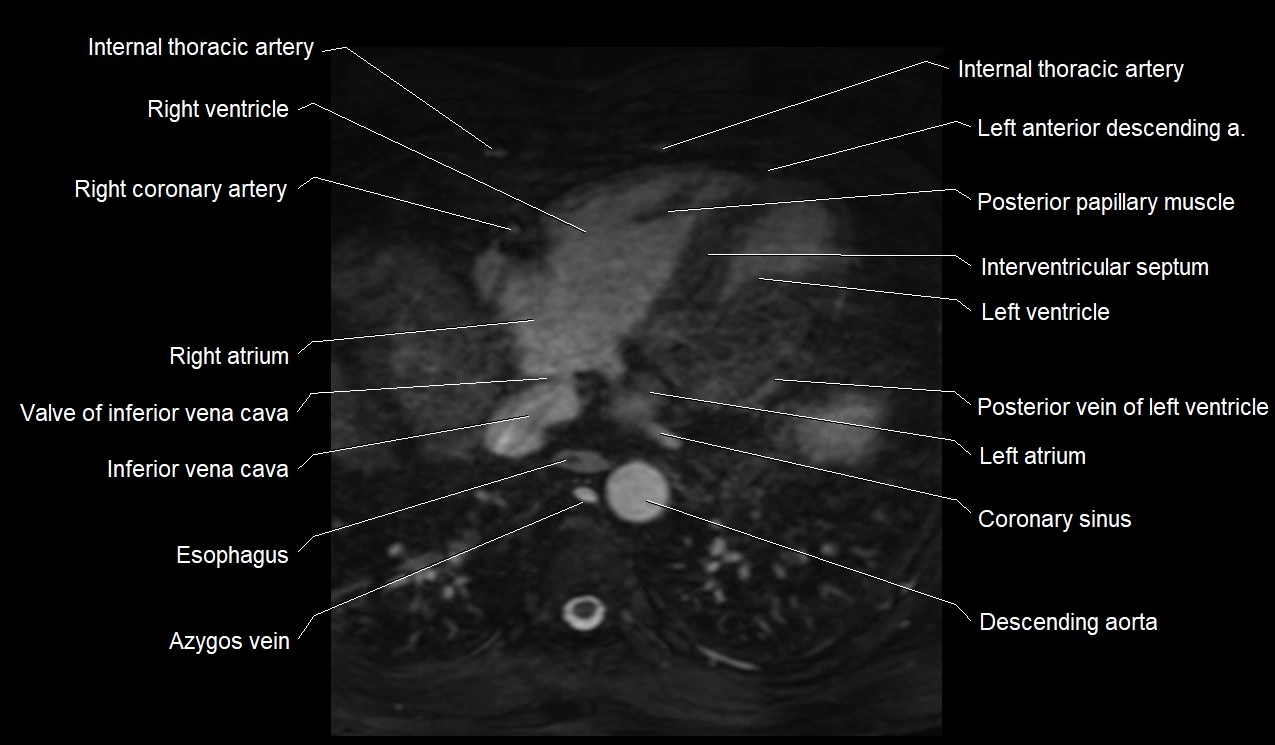

MRI image